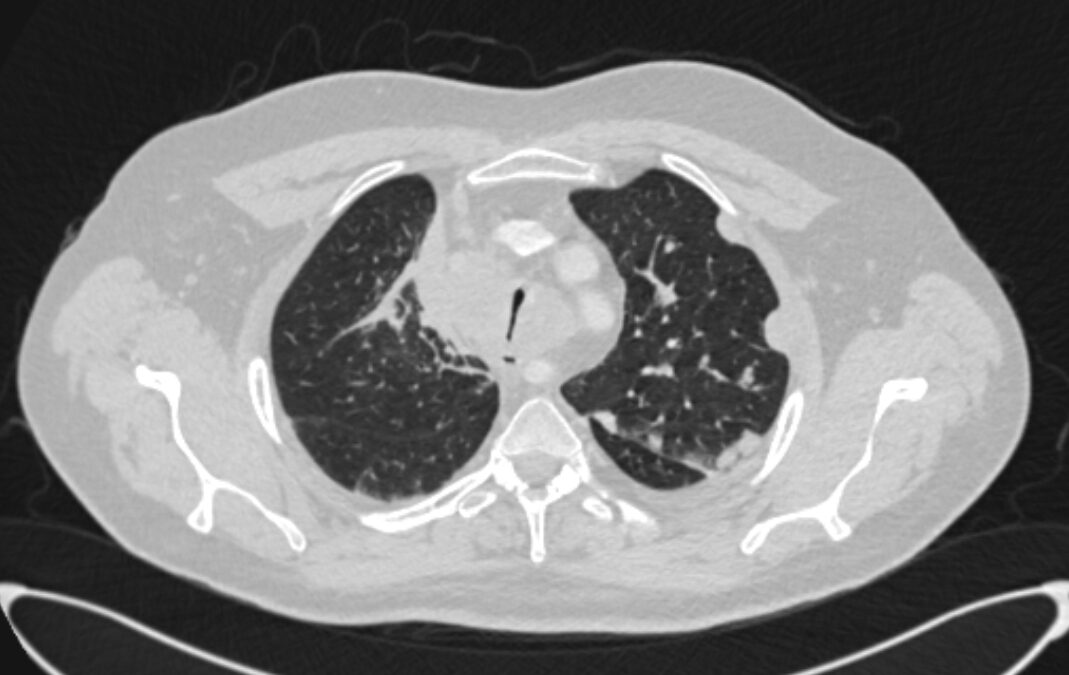

Клапанная бронхоблокация; Кровотечение из туберкулезных каверн легкого Больной 57 летний мужчина. В 2013 году был лечен по поводу туберкулеза легких. Несколько месяцев назад у него появилось кровохарканье с эпизодами кровотечения. Пациент постоянно находится на...